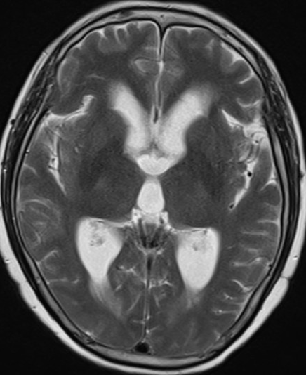

2013-5-16 MRI